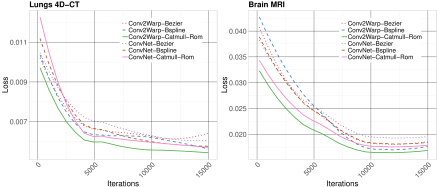

Comparison of Catmull-Rom spline with other spline-based resamplers (including B-spline) is presented in Fig. 2. It can be observed that Catmull-Rom spline has the lowest training losses for both lung and brain datasets.

A multi-modal normalized cross-correlation (NCC) metric is used as data term in our loss function. We propose to use a derived sum-of-squared difference (SSD) which guarantees maximization of NCC metric [4] and is written as with mean , standard deviation , the total number of pixels and (used to avoid division by zero). For obtaining a smooth deformation vector field we apply an -norm of the difference between the computed from the NL-DVF-R block and which is the previous upsampled input DVF to CWS block (see Fig. 1). Losses computed during pyramid levels in our CWS block are aggregated to the final loss. The resulting equation for the backward propagation is: where is the trade-off between the regularization and the data-term. In our experiments it is set to 0.001. We restrict the regularization to the interval to prevent over smoothing problem during training. Omitting this constraints results in failures which are documented in Fig. 2 of Suppl. Mat. (see plot for Conv2Warp-FullReg). The loss saturates after 6000 iterations. However, regularised models with the interval continue to minimise the loss function. Our constrained loss is optimized using Adam optimizer with learning rate .